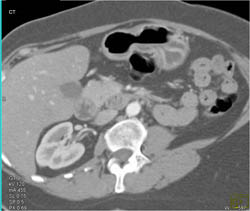

Diagnosis

Antral Cancer